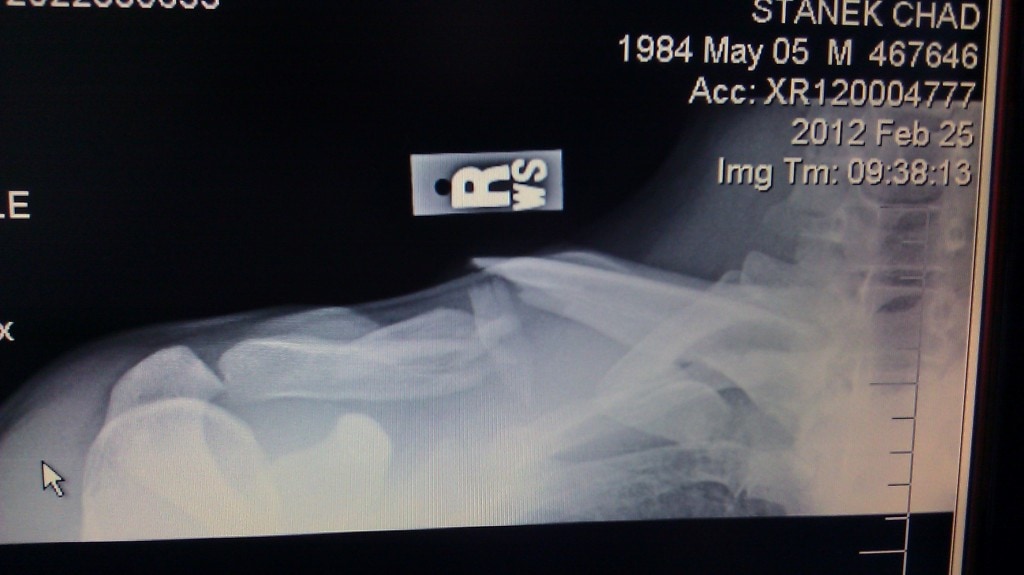

He reached into his shirt and felt the bone sticking out on his right shoulder. He skied over to one of the ski officials and requested medical help. He rode the sled straight into the ER at the base of the mountain.

After seeing three different specialists, he’s decided to have surgery tomorrow morning (3-1-12). He is going to the University of Chicago where they will put a plate in place to hold the 5 broken pieces of his clavicle together.

This was not his only option, but seems like the best way to go for him. He wears a heavy backpack daily for work (HVAC Technician) and hopes to be able to do so again without discomfort.